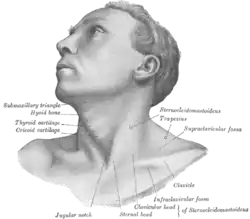

The supraclavicular lymph nodes can be felt in the supraclavicular fossa, shown here.

The supraclavicular lymph nodes can be felt in the supraclavicular fossa, shown here.